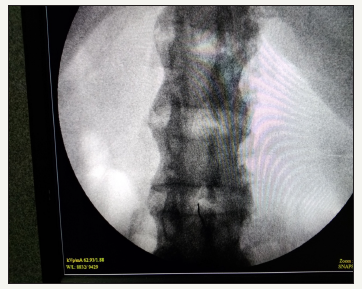

In Operation theater (OT), multipara monitors were attached. A wide bore i.e. line was secured and RL infusion was started. Difficult airway cart was kept ready. Patient was made to sit and under all aseptic precaution, Lumbar punctures were attempted at different spinal levels by median or paramedian approach through landmark technique, but it failed even after multiple attempts. So, it was decided to attempt fluoroscopic guided subarachnoid block under c-arm in same sitting position. An anteroposterior (AP) image of the lumbosacral spine Figure 1&2 showing minimal assessable window at L3-L4 intervertebral space (Figure 3) by variable degrees of lateral and oblique C-arm rotation was obtained. Subarachnoid space was approached in single prick with 25-gauge quincke-Babcock spinal needle using end on view between L3-L4 space. After confirming free flow of CSF, 0.5% Bupivacaine heavy 3.5ml was injected. Patient was immediately made to lie-down in supine position and a level of T10 was achieved. Throughout the surgery hemodynamic vitals were maintained. Surgery was completed uneventfully.

Figure 3:AP view from image intensifier showing fused vertebrae and end on view of spinal needle from minimal assessable space between L3-L4 vertebra through which subarachnoid block was approached.